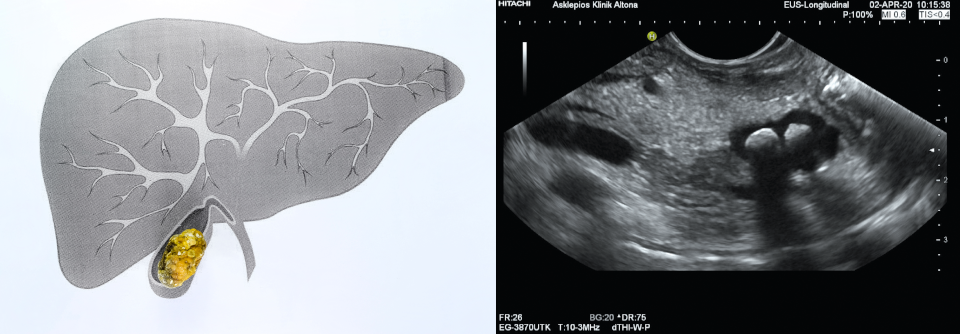

Dieser Frage gingen Kollegen um Aafke H. van Dijk von der chirurgischen Abteilung am Amsterdam University Medical Center nach. Sie nahmen 1067 Patienten mit Abdominalschmerzen und sonographisch nachgewiesenen Gallensteinen in eine randomisierte Multicenterstudie auf. Die…